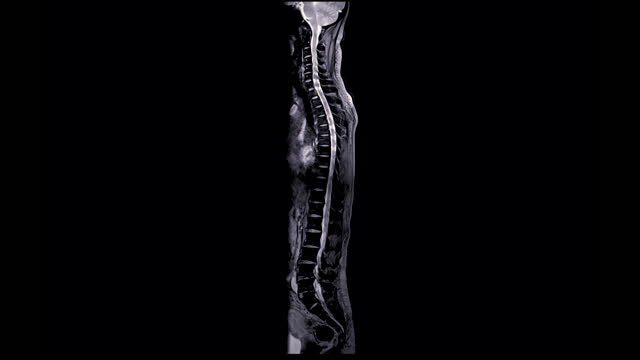

척추관협착증은 척추의 퇴행성 변화로 인해 발생합니다.

이 질환은 척추 내의 신경관이 좁아지면서 다양한 증상을 일으킵니다.

중요한 것은 모든 척추관협착증 환자가 수술을 필요로 하는 것은 아니라는 점입니다.

증상의 정도와 일상생활에 미치는 영향에 따라 치료 방법을 결정해야 합니다.